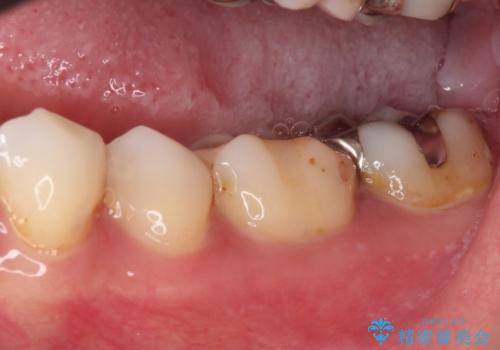

上顎は、元々の詰め物が小さく、欠けた範囲も大きくなかったため、セラミックインレーにて修復治療を行うこととしました。

一方下顎は、元々のむし歯の範囲が広かったため、長期的な予後を踏まえ、セラミッククラウンにて補綴治療を行うこととしました。

特に痛みはありませんでしたが、未然にしっかりとした処置を行うことで、今後むし歯の進行により神経組織が壊死するリスクを低減することが可能となります。